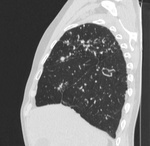

Пациент, впервые заболел в 02 году в ЗК, после рецидив в 07, потом в 11году. Сейчас состоит по активной группе с диагнозом: ФКТЛ легких , 1А (-)ГДУ. А по КТ оказалось, что все и не плохо.

Кроме ФКТ, думаю, что ещё и множество туберкулём. Или это очагами называете? Если туберкулёмы, то в 6-ке справа похоже на распад.